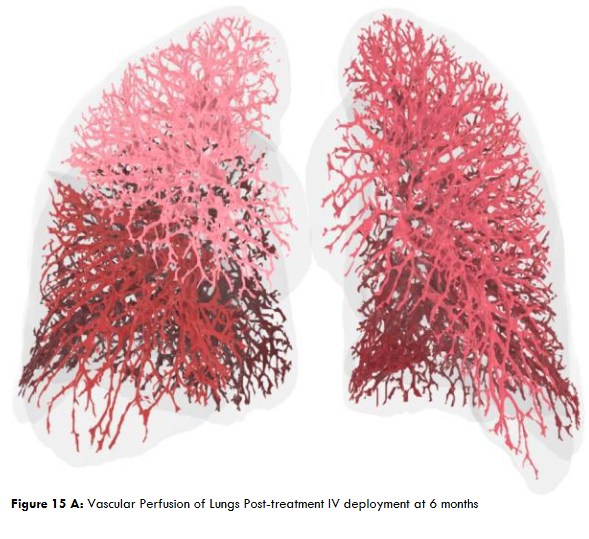

Figure 15A: Vascular Perfusion of Lungs Post-treatment IV deployment at 6 months. Figure 15B: Post IV deployment cSVF therapy in Long COVID-19 clinical trial NCT04326036 at 6 months. NOTE: Improved perfusion, throughout, but particularly in the lower distal lung. Figure 16: Restoration of the near terminal Tracheobronchial tree, pre-treatment showing blunting and loss of distal bronchiolar tree. Figure 16B: Post-treatment IV cSVF with elongation of distal bronchiolar tree at six months. NOTE: With this post-treatment changes with cSVF was an accompanying reduction in airway resistance and pressures within the lung parenchyma. Higher pressures in pre-treatment image were located in the Upper lobes (less efficient and higher pressures in pre-treatment), whereas the shift from upper to lower lung parenchyma accompanied Improve vascular supply and perfusion, and patients no longer experienced difficulties in inhalation capabilities.